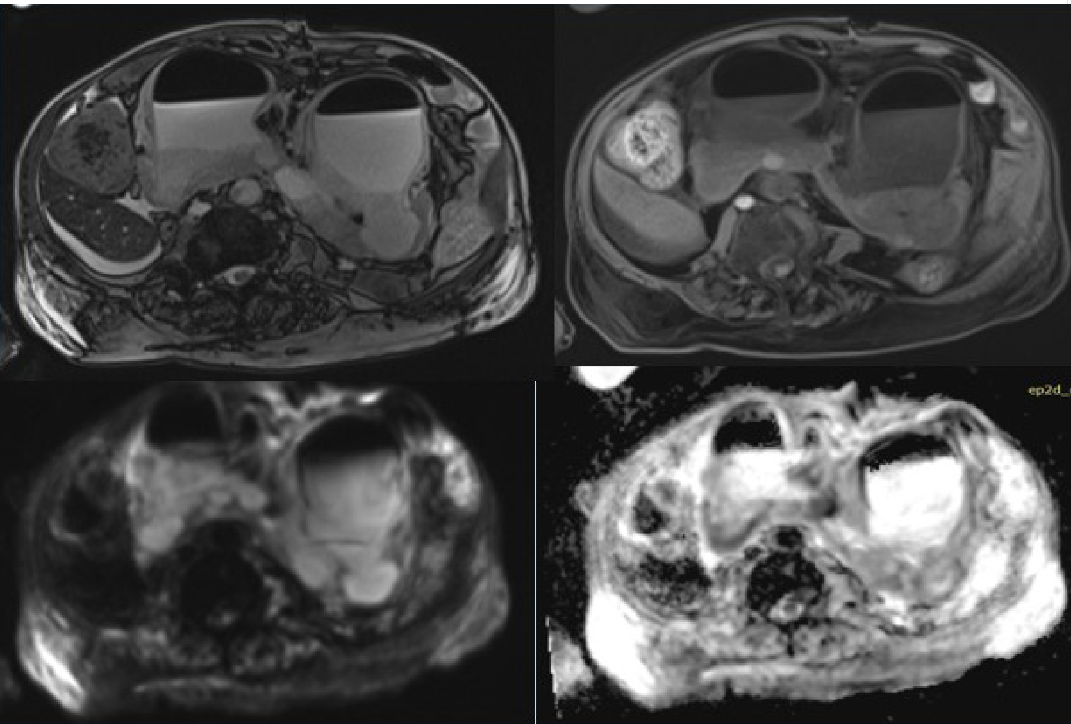

La falla renal limitaba la utilización de material contrastado, se decide realizar pielo-TC estudio adquirido en equipo Somatom Defininition 10, con técnica helicoidal y multicorte, realizando un barrido desde las cúpulas diafragmáticas hasta la porción superior de las crestas iliacas sin material de contraste, obteniendo imágenes axiales y reconstrucción MPR reportando en cortes coronal y sagital marcada dilatación de asas intestinales con material hipodenso y gas en su interior (Figura 2). Estudio se concluye con enfermedad renal crónica avanzada, ateromatosis de la aorta abdominal, colelitiasis y líquido libre en ambas goteras parietocolicas.

Se colocó catéter percutáneo guiado por ultrasonido como manejo mínimamente invasivo, para drenaje de material dentro de bolsa hidronefrótica y toma de muestras para cultivo

Figura 2